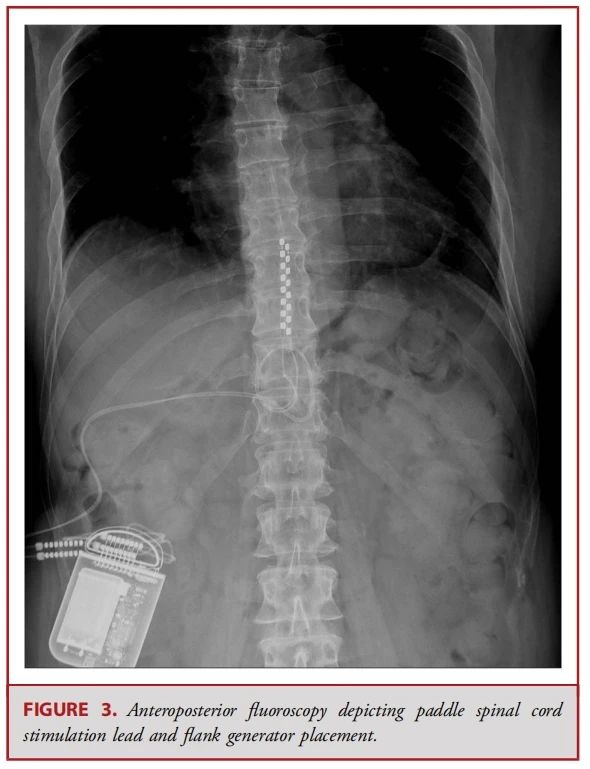

● 经皮电极通常由 8 个球形接触点组成,而鳍状电极则通常具有16至20个接触点,且所有接触点都平铺在硬膜表面(见图 1-3)。经皮电极通常通过改良版的 Tuohy 导管进行插入(见图 4)。在使用失去阻力法进入硬膜外腔后,电极在透视引导下被推进至与疼痛部位相应的脊髓节段(见图 5)。经皮电极和鳍状电极在镇痛效果上具有相似的疗效。经皮电极植入属于较低侵入性的手术,术后并发症的发生率较低(2.2%,相较于鳍状电极3.4%),因此对于合并症较多的患者来说,是一种更为理想的选择。鳍状电极虽然更具侵入性,但与圆柱形经皮电极相比,电极移位的发生频率较低。由于鳍状电极具有更多接触点,因此可以实现更为精准和高效的刺激。